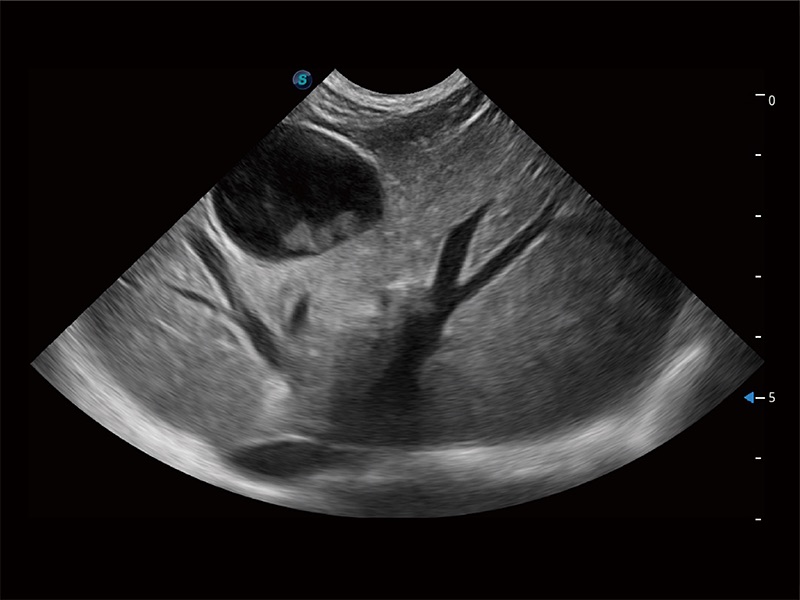

ProPet 80 配备了丰富的心脏探头群、先进的成像技术和专业的心脏测量工具,可帮助动物医生为不同体型和生理结构的动物提供心脏和心肌功能的全面评估。

一键自动识别膀胱壁及自动测量膀胱容积,不受膀胱形状和大小的限制,帮助医生快速精准获得测量的数据。

ProPet 80 全新的动物超声智能软件和丰富的探头群,为动物医生提供了高清晰度和精细分辨率的图像,无论在宠物、马科、畜牧还是实验室动物等应用中都可以轻松应对,为您的日常工作带来满意的体验。